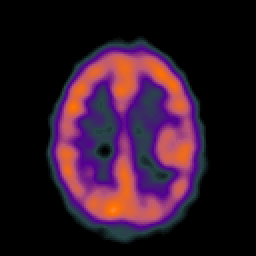

Metastatic bronchogenic carcinoma: Perfusion SPECT -- Slice #14

[Home][Help][Clinical] Slice 14